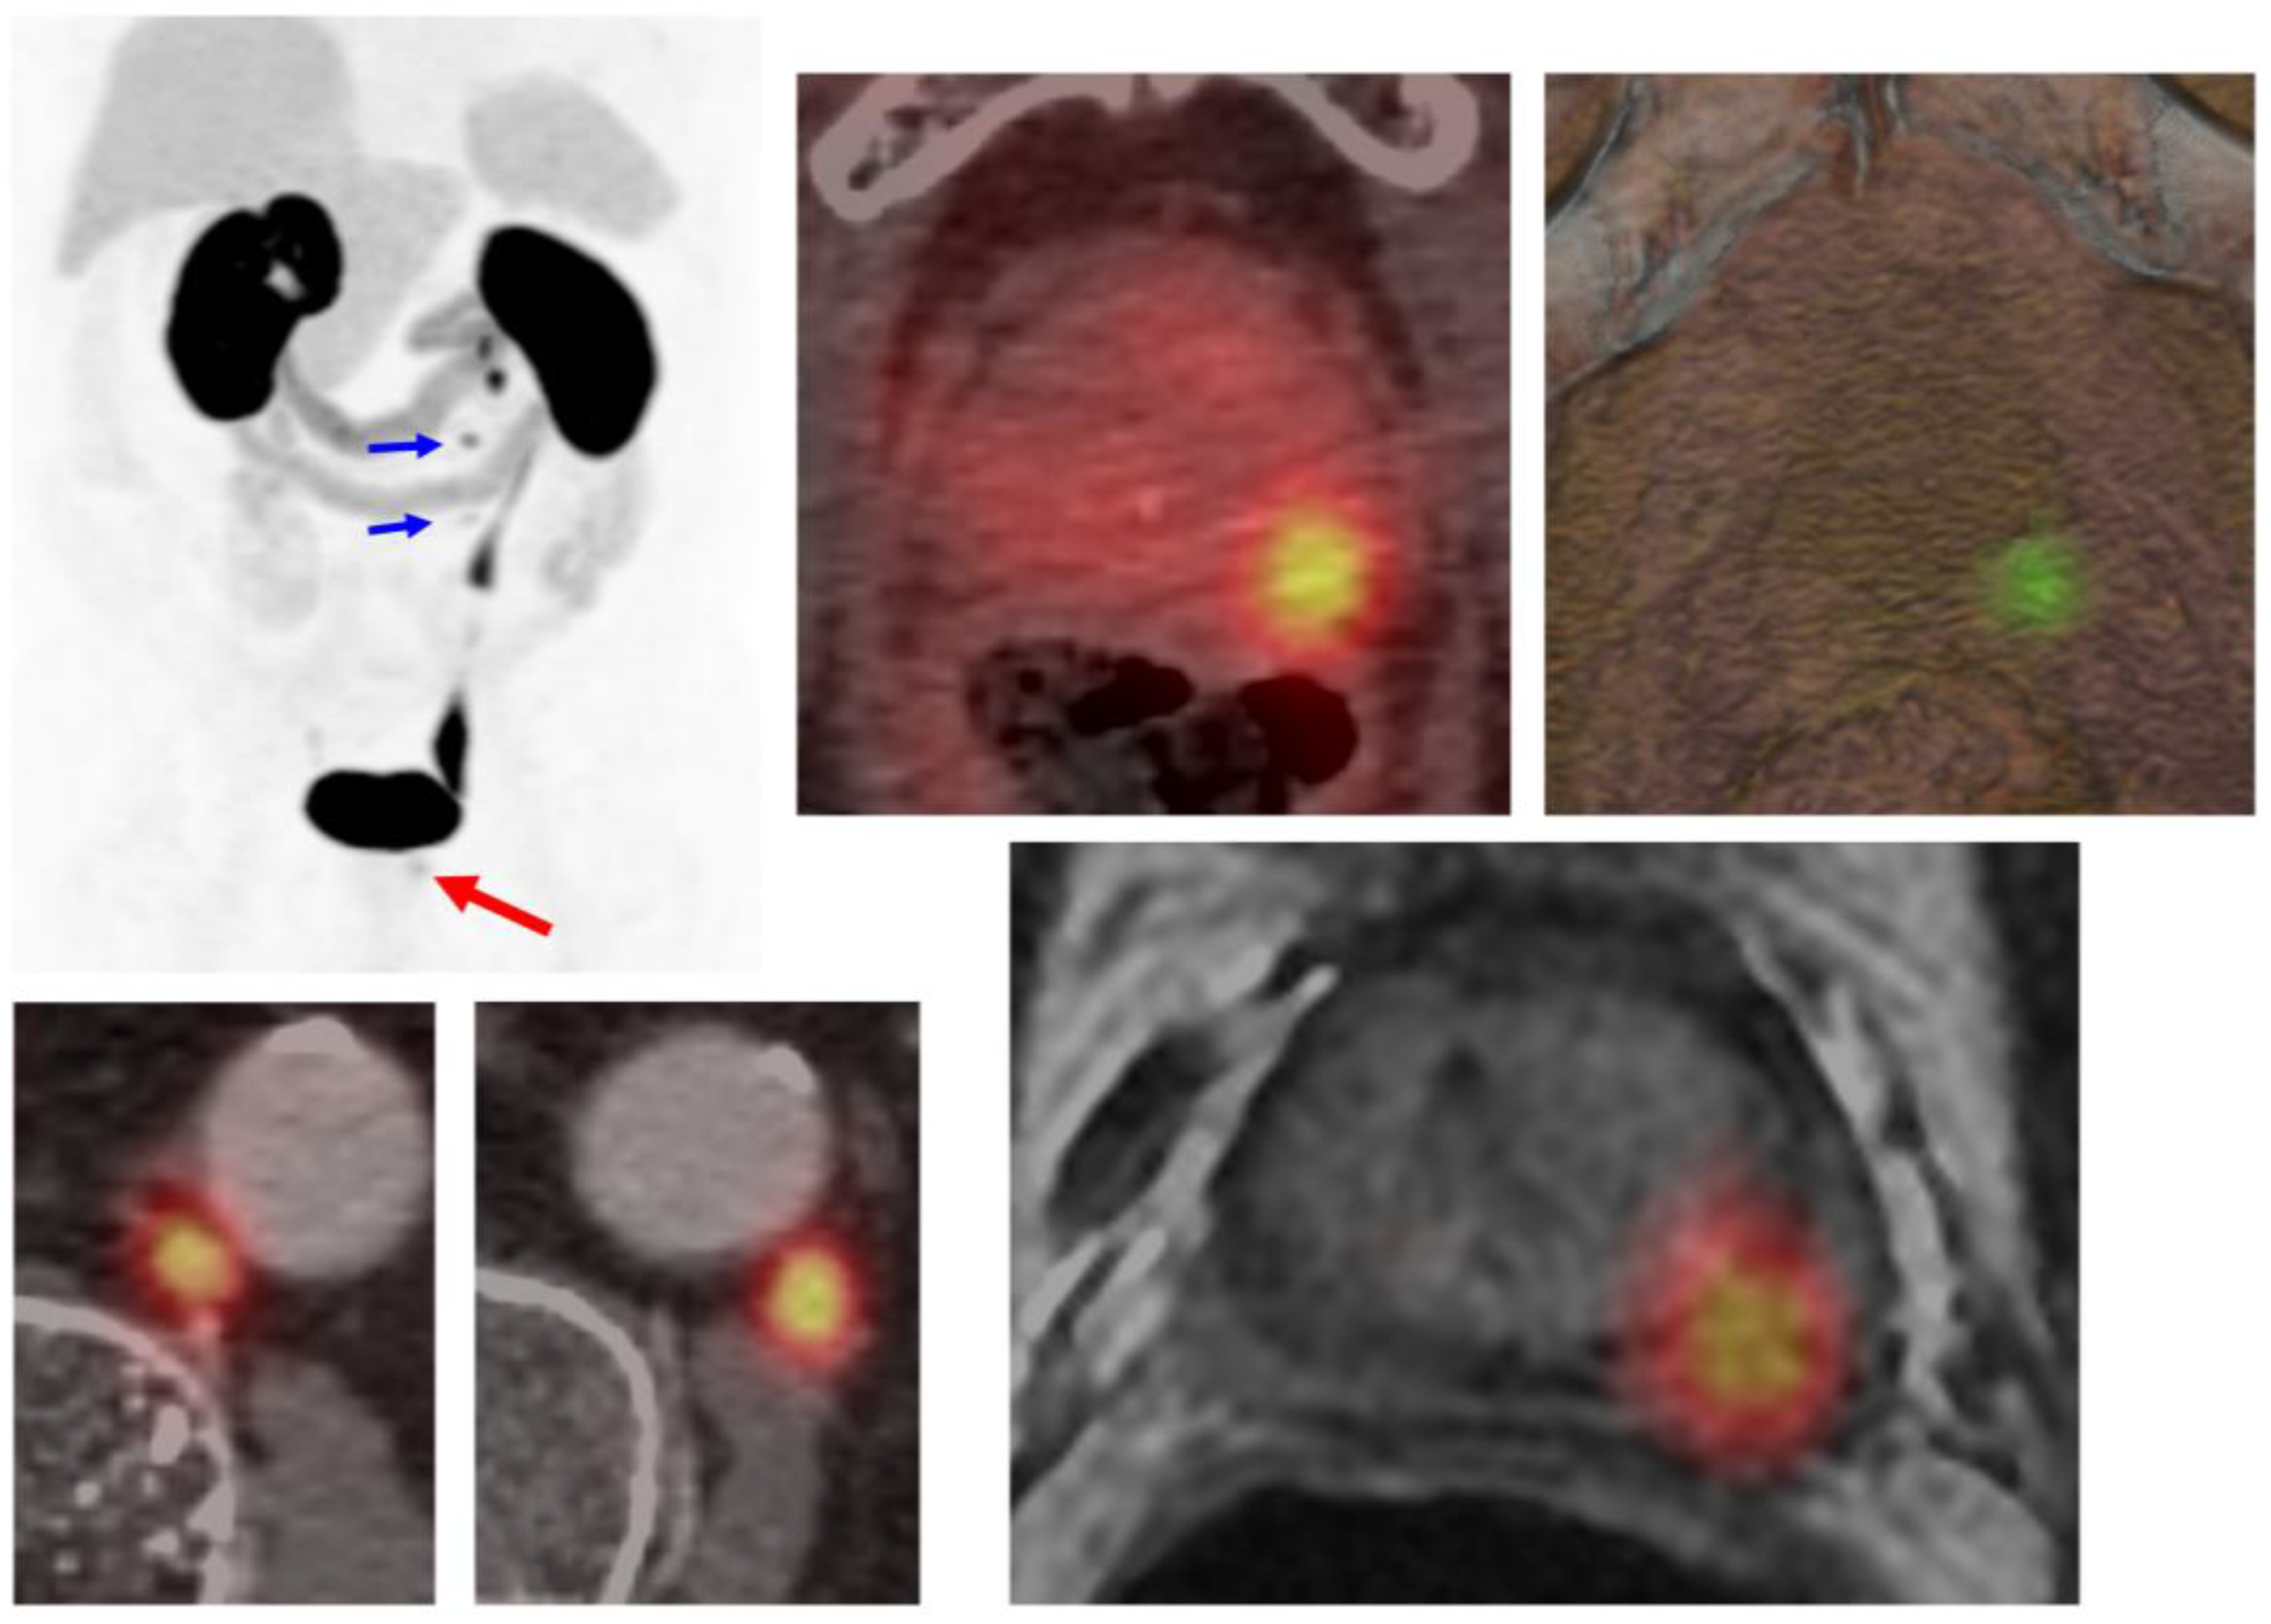

4.1. Local Recurrence

- Awiwi, M.O.; Gjoni, M.; Vikram, R.; Altinmakas, E.; Dogan, H.; Bathala, T.K.; Naik, S.; Ravizzini, G.; Kandemirli, S.G.; Elsayes, K.M.; et al. MRI and PSMA PET/CT of Biochemical Recurrence of Prostate Cancer. Radiographics 2023, 43, e230112. [Google Scholar] [CrossRef] [PubMed]

- Freitag, M.T.; Radtke, J.P.; Afshar-Oromieh, A.; Roethke, M.C.; Hadaschik, B.A.; Gleave, M.; Bonekamp, D.; Kopka, K.; Eder, M.; Heusser, T.; et al. Local recurrence of prostate cancer after radical prostatectomy is at risk to be missed in 68Ga-PSMA-11-PET of, P.E.T./.C.T.; PET/MRI: Comparison with mpMRI integrated in simultaneous, P.E.T./.M.R.I. Eur. J. Nucl. Med. Mol. Imaging 2017, 44, 776–787. [Google Scholar] [CrossRef]